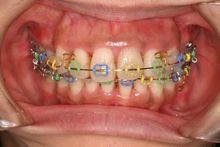

初診時正面

初診時の口腔内写真です。上顎の中切歯に翼状捻転が認められます。また、下顎にも叢生が認められます。スペースの不足量は上顎5mm、下顎10mmでした。

治療開始12ヵ月後正面

治療開始12ヶ月後の口腔内写真です。下顎の叢生はほぼなくなっています。矯正用アンカースクリューを固定源として上顎前歯部を後方に牽引しているところです。カラーモジュールを使用しています。本症例では青、黄、緑ですが、赤、金、銀、紫など20色程度あります。ご希望の患者様はお申し付けください(無料です)。